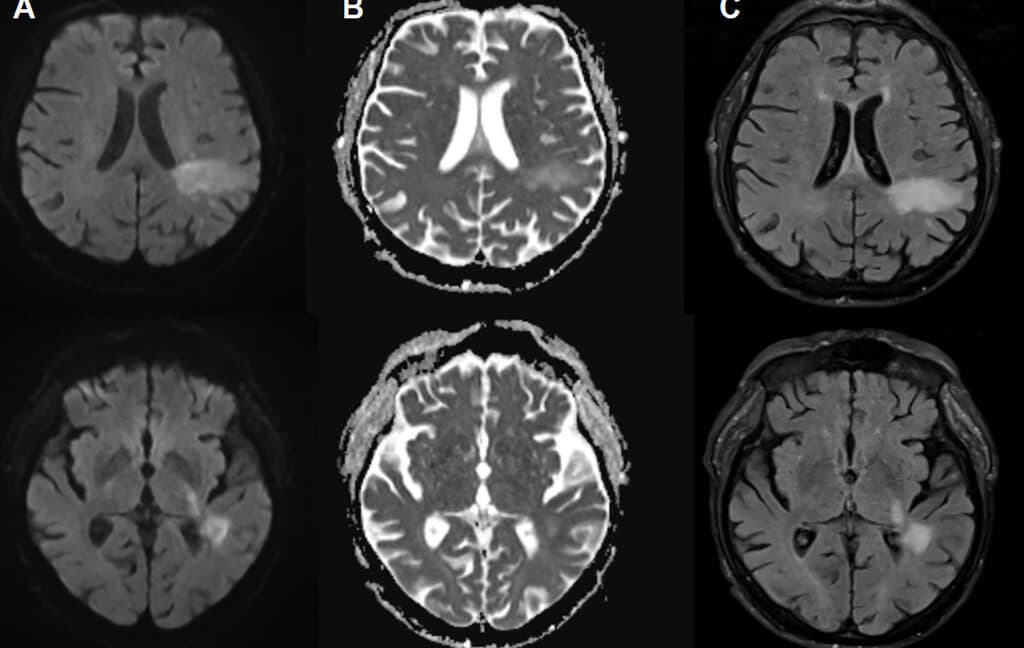

PML occurs when the modified JC virus infiltrates the brain, damaging specific brain cells, including those responsible for creating myelin sheaths that protect nerve cells. This results in significant demyelination, leading to nerve cell dysfunction and death. Diagnosing PML typically involves identifying distinctive brain lesions through imaging and detecting JC virus DNA in cerebrospinal fluid. Symptoms of PML can resemble those of a stroke or multiple sclerosis, including speech and visual impairments, motor dysfunction, and seizures.

Initially, doctors suspected uremic encephalopathy—a decline in brain function due to toxin buildup from kidney failure. Although treated with dialysis, the patient's condition deteriorated, leading to brain imaging that revealed lesions associated with PML. Subsequent tests confirmed the presence of the JC virus in his cerebrospinal fluid, and the patient passed away two days later.